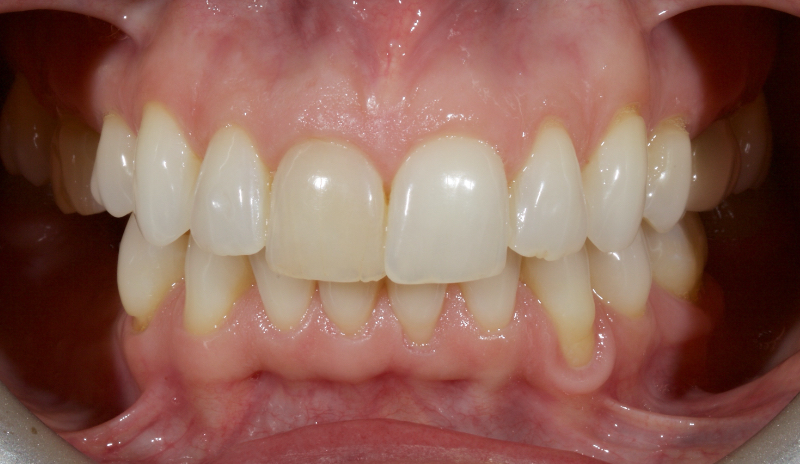

This article explores a more modern, minimally invasive approach to discolored non-vital teeth using the “modified walking bleach” approach. Figure 3 (before treatment) and Figure 4 (after treatment) show an example of this highly conservative approach.